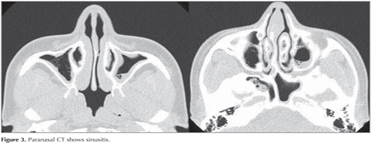

Paranasal CT revealed mucosal thickening as well as soft tissue densities consistent with sinusitis in the mucosa of maxillary, ethmoidal, sphenoidal, and frontal sinuses (Figure 3). Dermatological examination revealed no fungal infection of nails.

Figure 3